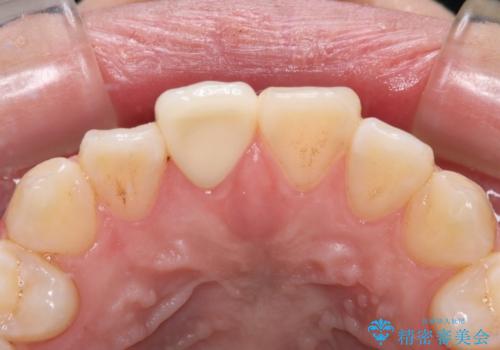

土台の形を整えて、精度の高いシリコーンによる型どりを行いました。

セラミックが入るまでの間は仮歯にしています。

樹脂の材料では再現できない自然な前歯に仕上がりました。